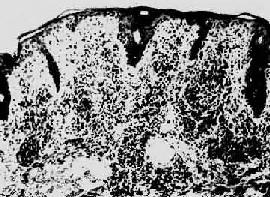

第二期梅毒第一期梅毒如不治疗,即使下疳愈合,潜伏于体内的螺旋体仍能继续繁殖,在感染后第8~10周左右大量进入血循环,引起全身广泛性皮肤粘膜病变,即梅毒疹(syphilid)。通常表现为口腔粘膜红斑、丘疹、躯干、四肢、掌心和足心的斑疹、丘疹和口唇、外阴、肛周的扁平湿疣(condyloma lata)。后者表现为暗红色突起的平坦斑块。所有梅毒疹的组织学变化皆为淋巴细胞和浆细胞浸润构成的非特异性炎及闭塞性血管内膜炎和血管周围炎(图18-26),扁平湿疣则尚有表皮增生和角化不全。凡梅毒疹病灶内皆有苍白螺旋体。第二期梅毒有全身性淋巴结肿大,镜下为非特异性炎。少数患者可发生亚急性脑膜炎、虹膜炎或肝炎,以及免疫复合物反应所引起的膜性肾小球肾炎。梅毒疹也可不治“自愈”,但患者实际陷入隐性梅毒阶段,若不治疗,多年后30%的患者将发生第三期或晚期梅毒。第二期梅毒若予治疗,将阻止其向第三期梅毒发展。

图18-26 梅毒疹

真皮呈致密的淋巴细胞及浆细胞浸润(采自Muir)